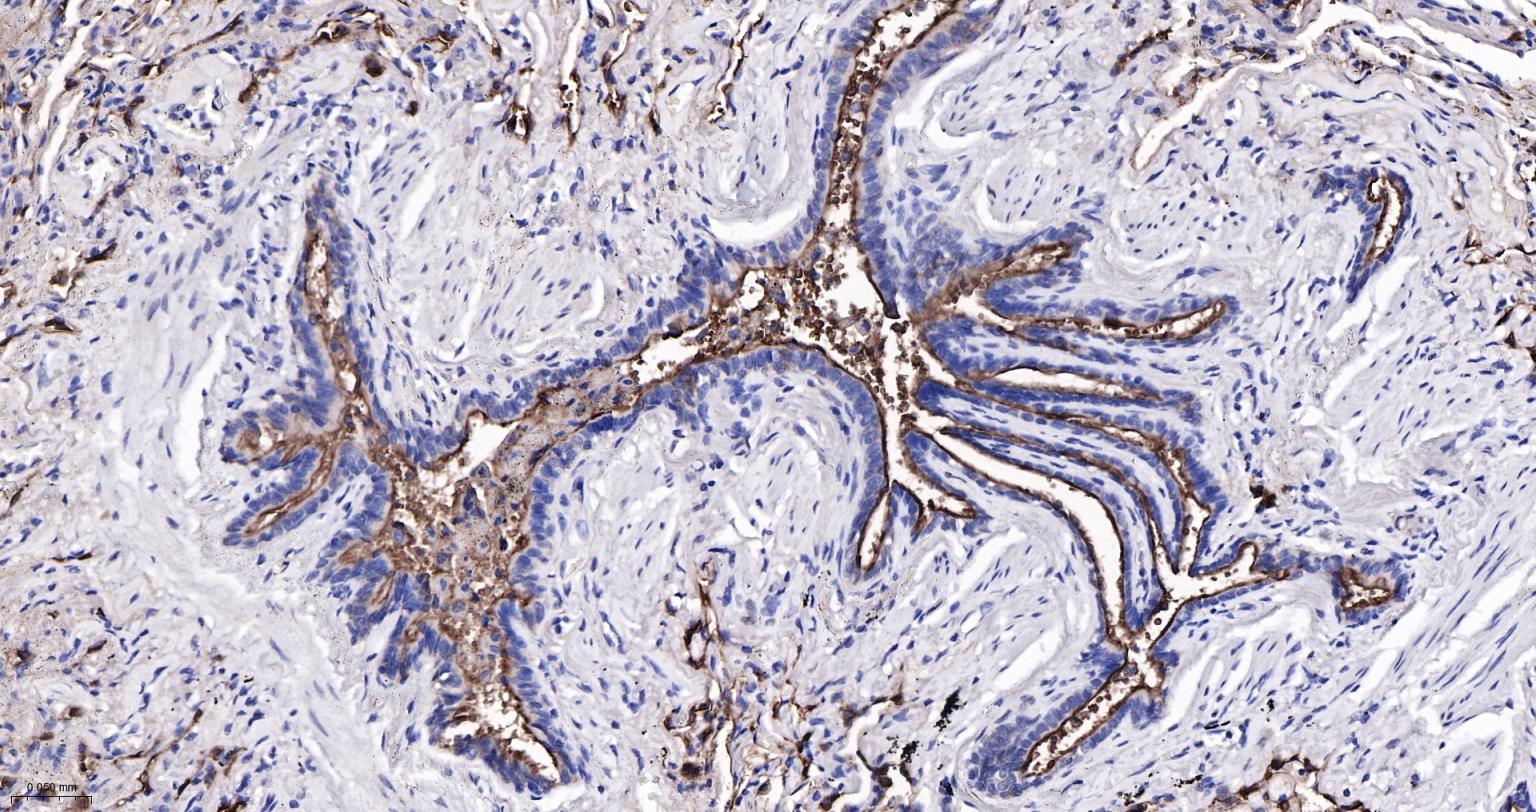

Paraformaldehyde-fixed, paraffin embedded Human Endometrial; Antigen retrieval by boiling in sodium citrate buffer (pH6.0) for 15 min; Antibody incubation with MUC1 Monoclonal Antibody, Unconjugated(bsm-52576R) at 1:200 overnight at 4°C, followed by conjugation to the bs-0295G-HRP and DAB (C-0010) staining.